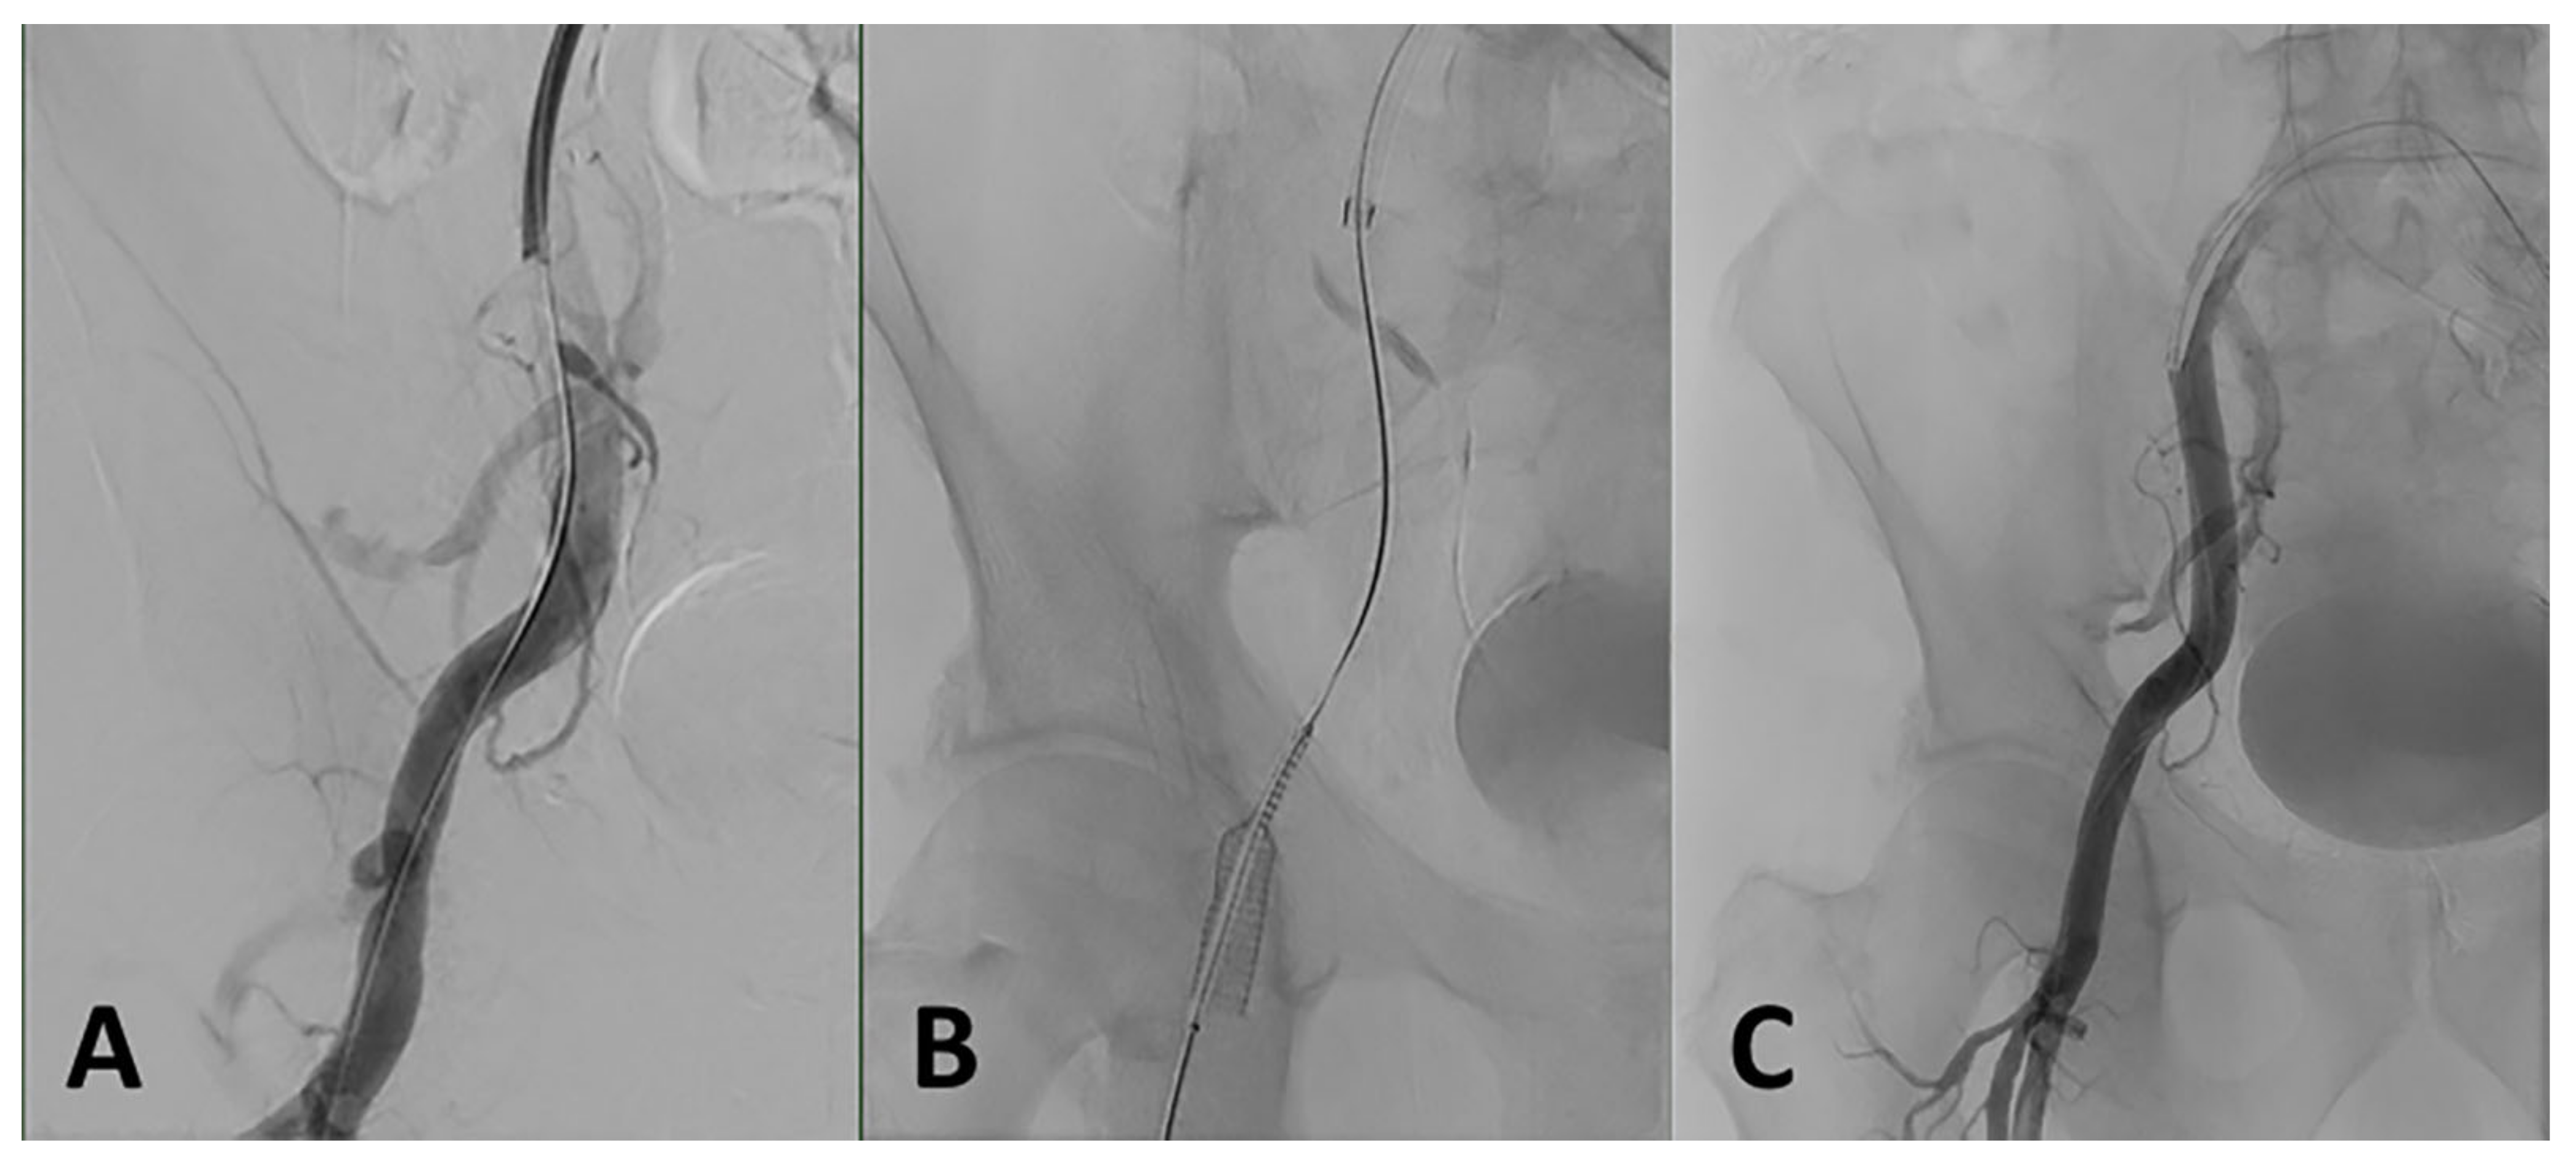

3.6.2. Iliofemoral Dissection or Rupture